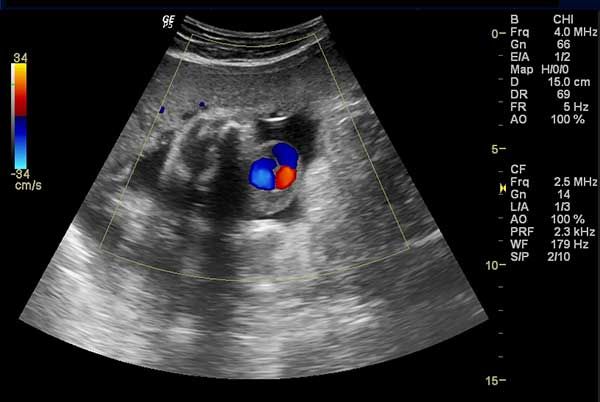

From these images, what would you diagnose in this patient?